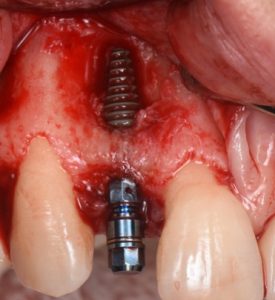

This video demonstrates implant placement in the esthetic zone combined with simultaneous guided bone regeneration (GBR). The case focuses on surgical decision-making, specifically how to determine when a staged approach is indicated versus when simultaneous implant placement and GBR can be predictably performed.

The procedure is presented step by step, including flap design and management, defect assessment, membrane selection and stabilization, flap advancement, and suturing techniques. Emphasis is placed on achieving tension-free closure and maintaining hard and soft tissue contours critical for esthetic success.